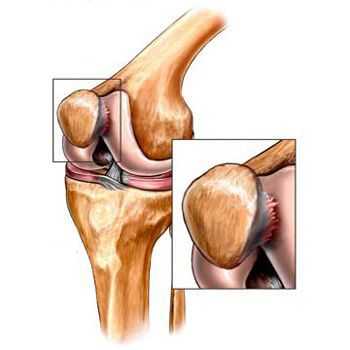

Киста наружного мениска обычно возникает в средней трети наружной части мениска, реже – в области переднего или заднего рога. Киста менисков не соединяется с капсулой сустава, которая под давлением растущего опухолевидного образования постепенно истончается. Как правило, выпячивание располагается сзади от наружной боковой связки. Киста внутреннего мениска выпячивается сзади или спереди от внутренней боковой связки, реже выдается через толщу связки. Длительно существующая киста мениска вызывает дегенеративные изменения костной ткани и приводит к развитию деформирующего артроза.

В травматологии и ортопедии диагноз кисты менисков выставляется на основании клинической картины, результатов УЗИ коленного сустава, артроскопии или МРТ коленного сустава. При развитии деформирующего артроза мыщелка большеберцовой кости выявляются характерные изменения на рентгенограммах (симптом Раубера-Ткаченко).